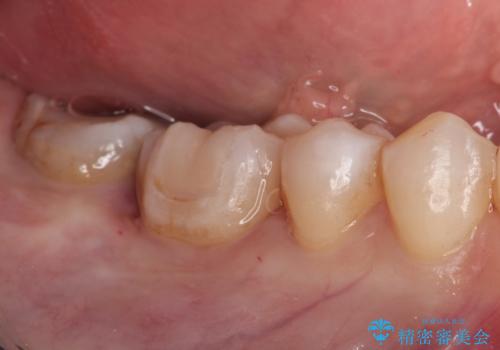

メタルフリー セラミックインレーによる治療

- 金属の詰め物を白くしたいと来院された患者様です。

セラミックインレーによって治療を行いました。

当院でのセラミックインレーはすべてe-maxと呼ばれる高強度セラミックにて製作されます。

また、製作方法もプレスと呼ばれる方法を用いることで精度を高めています。